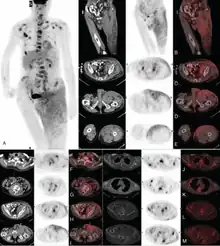

A Case Report |thumb|right|Due to the rarity of EMPD and lack of clinical knowledge, the disease is not very commonly diagnosed.[8] Patients are often misdiagnosed with eczema or dermatitis[8] and a delay of 2 years is expected from the onset of symptoms before a definitive diagnosis has been reached.[8]